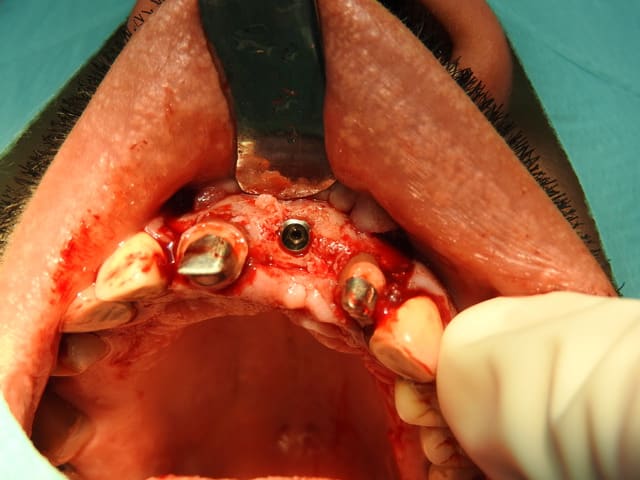

la photo de la pose de l'implant faite par un confrère sur le dernier cas

j'ai toujours une grade frustration à ne pas voir directement le résulta de la greffe quand je ne fais que cette dernière et que les correspondants posent eux même l'implant

temps "greffe" et temps "pose implant"

salut, l'implant n'est il pas un poil trop vestibulaire?

Bien vu. On ne voit pas bien sur la photo mais le rebord palatin de la crête alvéolaire arrive en mésio distale de l'édentement et plonge d'au moins 3mm à la verticale; c'était de la bouillie,ce rebord palatin, j'avais prévu un diamètre 4.1 à l'aise au scan, ce fût 3.6mm pour conserver 1mm de corticale.

2 possibilités: soit je pose en situation théorique et j'ai un comblement pas forcement simple à faire en palatin

soit je pose au centre de ma greffe donc légèrement vestibulaire parce que le projet esthétique le permet (notamment parce que le patient découvre à peine le rebord incisal).

J'ai opté pour la solution 2, la suite en photo + tard.